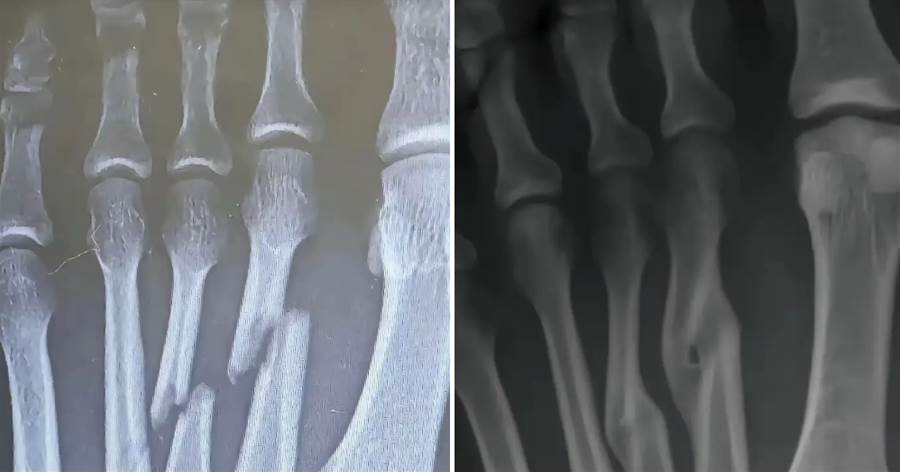

那張X光片靜靜躺在醫生手中,清晰顯示著第三蹠骨的斷裂與錯位——這是李阿嬤三個月前拒絕手術時留下的影像。當時,家人們圍在病床邊心急如焚:「媽,這骨頭都錯位了,不開刀會落下終身殘障的!」

三個月裡,兒女們每日提心吊膽。看著母親腫脹未消的腳踝,看著那明顯凸起的部位,他們已做好照顧殘障老人的準備。直到復查那天,新的X光片讓所有人都愣住了——原本錯位的斷骨,竟在未手術的情況下,奇跡般地長合在一起了。

「這……」醫生推了推眼鏡,仔細比對著新舊兩張片子,「雖然癒合處有輕微隆起,關節面也略顯不平,但確實自然癒合了。」他指著片子解釋:「人體骨骼本身就有強大的自愈能力,手術的鋼釘鋼板只是幫助復位,真正讓骨頭連線的,還是身體自身的成骨細胞。」